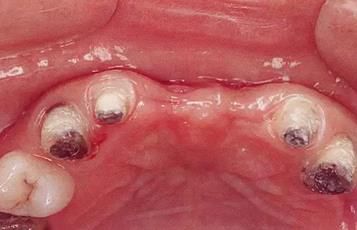

360截圖20170422101910161.jpg

▲圖7-1

對上頜前牙進(jìn)行初期治療后的咬合面觀。右上2,3存在炎癥。